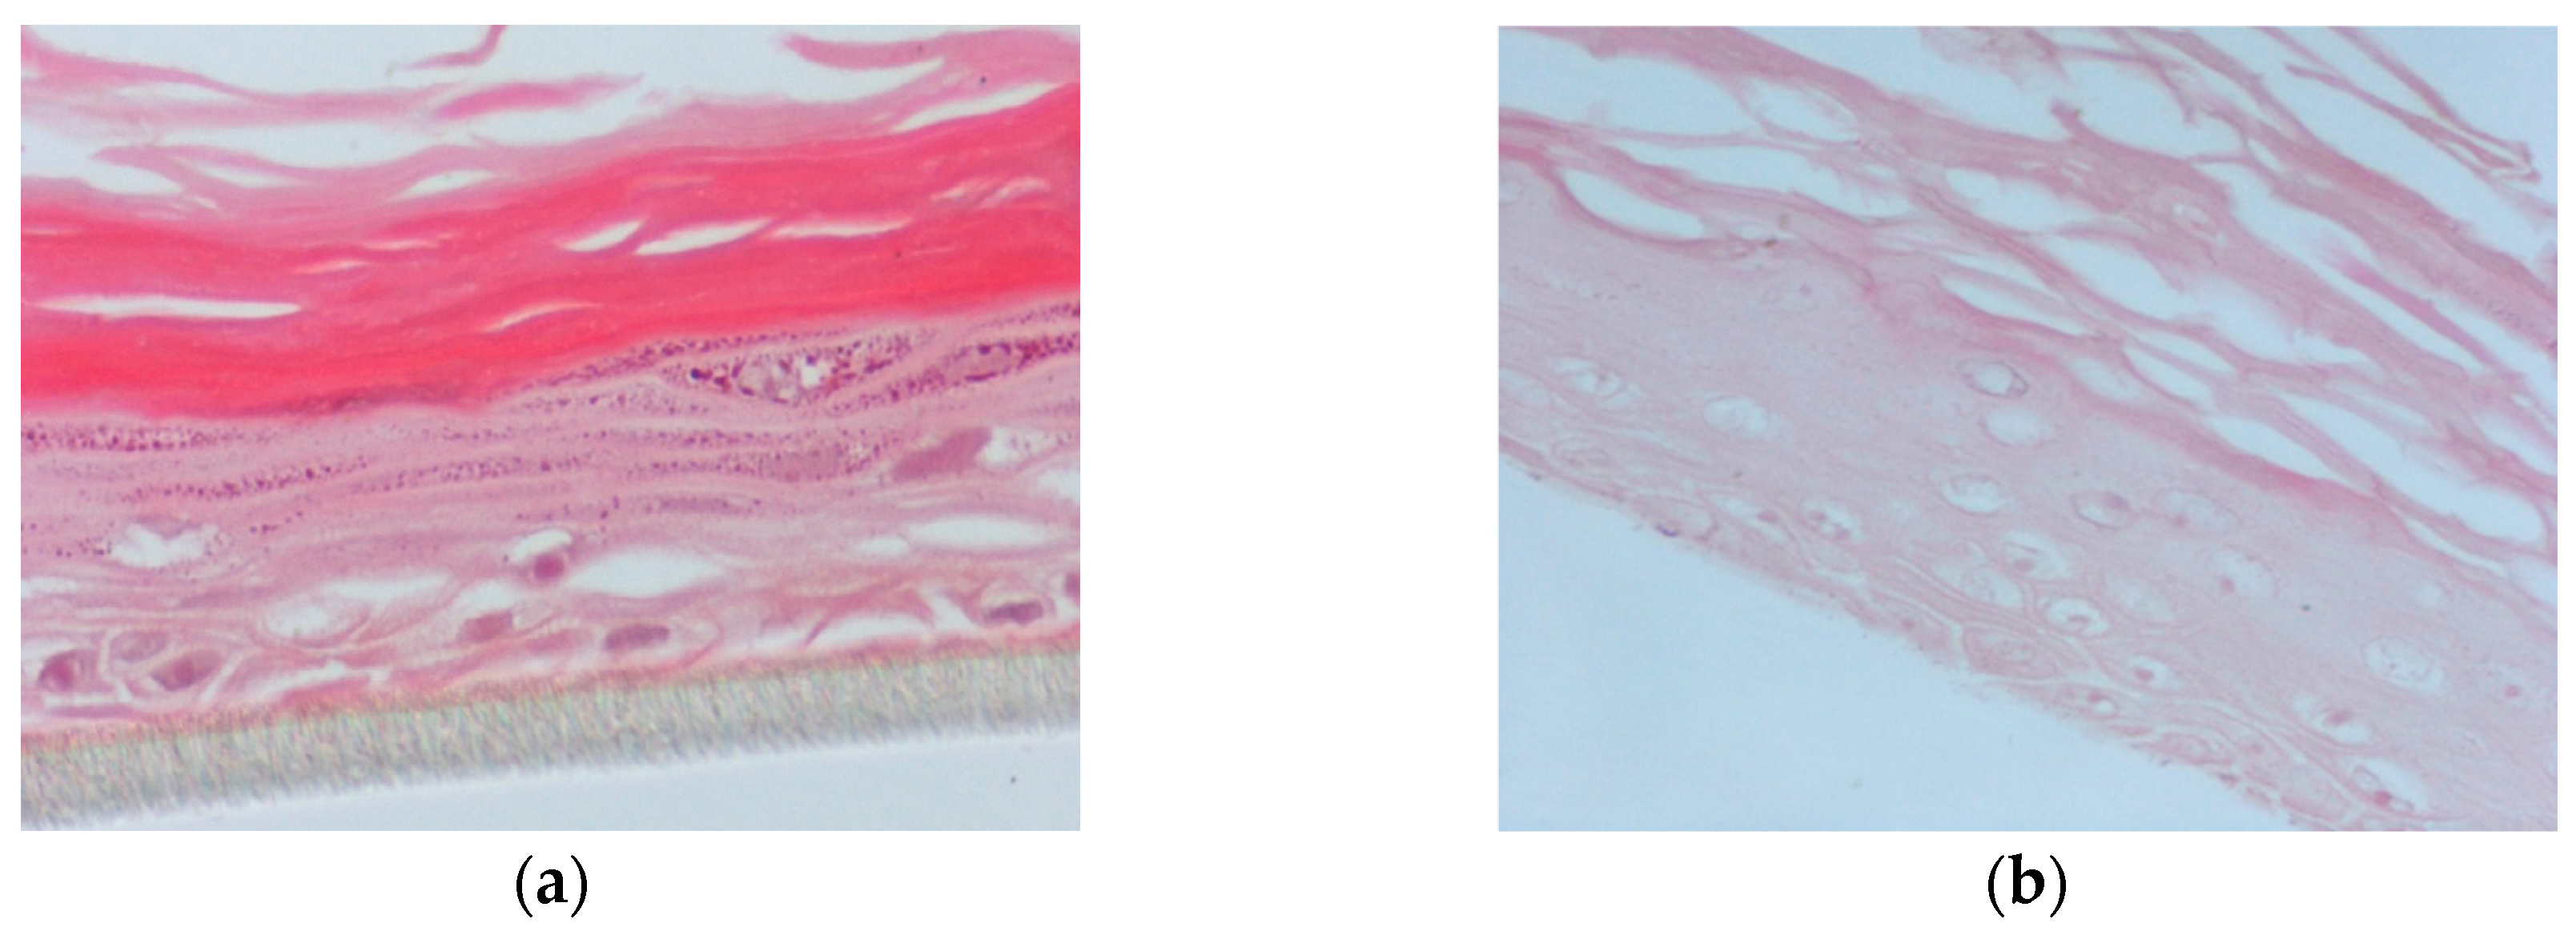

2.11. Human Reconstituted Skin Tissue Model (EpiDermTM EPI-200)

2.12. Treatment and UVB Irradiation of EpiDermTM EPI-200

2.14. Immunohistochemistry (IHC)

3.4. Propolis Extracts Inhibit UVB-Induced Overexpression of Matrix Metalloproteinases (MMPs) in a Human Reconstituted Skin Model